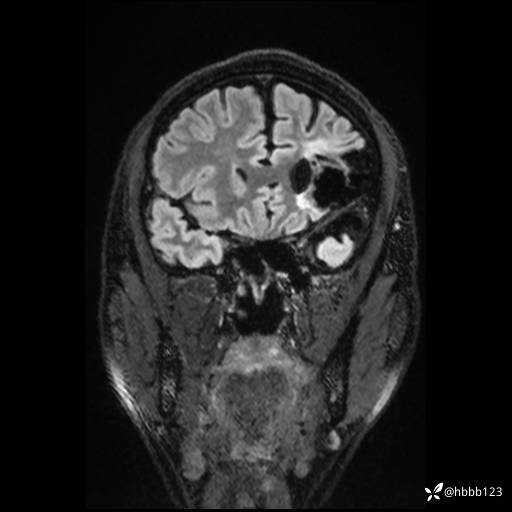

CUBE FLAIR冠状位: